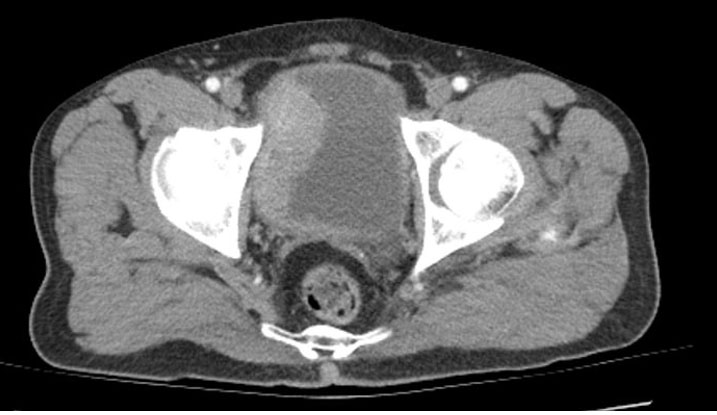

A 51-year-old male patient visited the urology outpatient clinic due to severe dysuria. It was discovered that he had previously under gone non-contrast CT because of macroscopic hematuria, which identified a tumor-like mass approximately 6 cm in diameter on the right lateral wall of the bladder (Figure 1). Consequently, the patient had a TUR of the tumor three weeks earlier and was discharged without any complications. His medical history included type 2 DM, diagnosed a decade ago. During the physical examination, the patient showed diffuse tenderness and pain in the suprapubic area. The patient had no fever at the time of admission. Laboratory results indicated a leukocyte count of 13,230/mm³ (reference: 4,300–10,300/mm³), a glucose level of 175 mg/dL (reference: 70–110 mg/dL), C-reactive protein of 14.8 mg/dL (reference: 0–0.5 mg/dL), HbA1c of 8.6% (reference: 4%–6%), and a creatinine level of 2.14 mg/dL (reference: 0.5–1.3 mg/dL). Urine analysis showed +3 erythrocytes and +3 leukocytes upon microscopic examination. His preoperative urine culture was sterile. The biochemical urine analysis revealed +2 protein and +3 glucose. No abnormalities were found in the urinary system ultrasonography (US). Given the initial diagnosis of a complicated UTI, a non-contrast abdominopelvic CT was conducted. On CT, diffuse thickening of all bladder walls and the presence of intramural air densities were noted within the bladder lumen, particularly in the area of the previous TUR on the right lateral bladder wall (Figure 2). The patient was admitted to the urology unit. Urine and blood cultures were taken. Intravenous broad-spectrum antibiotic treatment was initiated with meropenem at 1000 mg twice daily and moxifloxacin at 400 mg once daily. An 18 Fr urethral catheter was inserted for bladder drainage. Following catheterization, pneumaturia was observed (Figure 3). Bladder irrigation was conducted using normal saline. During the irrigation process, thick, foul-smelling infected urine containing solid particles was observed draining from the bladder (Figure 4). Irrigation continued until the urine was clear. During the follow-up in the ward, intermittent blockage of the catheter was noted. Therefore, daily bladder irrigation was continued. No microbial growth was detected in either urine or blood cultures. After 14 days of intravenous antibiotic treatment and continuous bladder drainage, the patient’s symptoms completely resolved, and laboratory values normalized. Follow-up imaging showed complete resolution of the previously observed diffuse bladder wall thickening and intramural air densities, and the patient was discharged in good condition (Figure 5).

Figure 2: CT image at the pelvic level taken three weeks post-TUR. The red arrow points to the presence of intraluminal air density with in the bladder, the blue arrow high lights intramural air density, and the yellow arrow illustrates the diffuse thickening of the bladder wall.